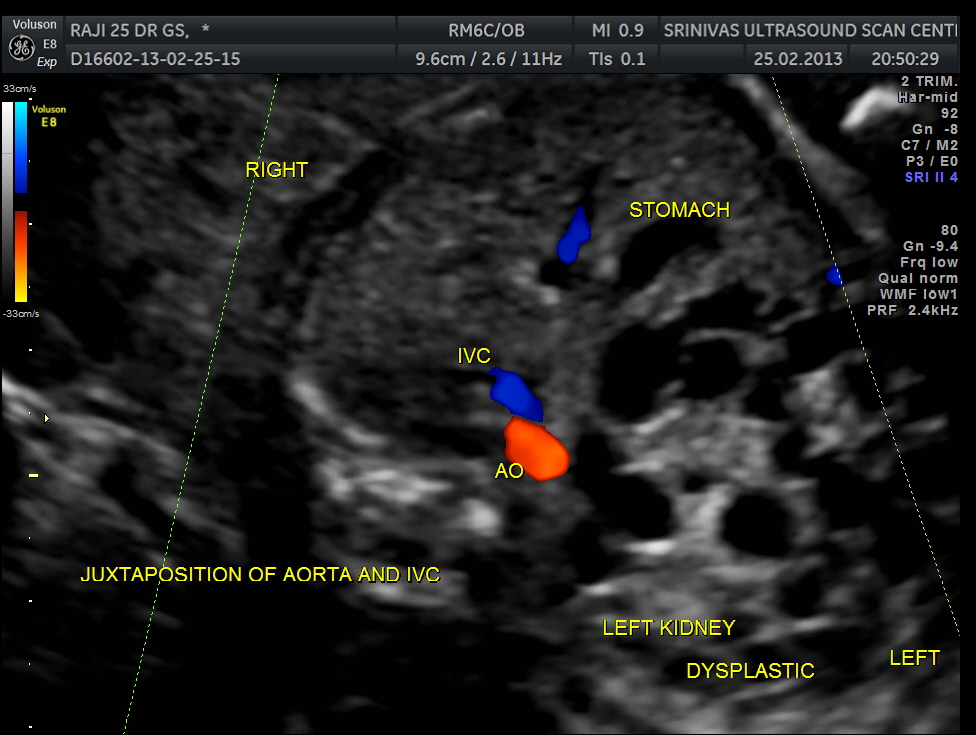

Abdominal transverse view shows aorta and ivc in juxtaposition and on the right side . This is suggestive of heterotaxy – right atrial isomerism. Grossly enlarged dysplastic left kidney is also seen. Right fetal kidney is difficult to visualise in this view. Stomach is in the midline. Heart is on the right side of the chest- dextrocardia

In right atrial isomerism, both atria of the heart are morphological right atria leading to associated abnormalities in the pulmonary venous system. In addition, individuals with right atrial isomerism develop asplenia, a mid-line liver, malrotation of the small intestine and the presence of two morphologic right lungs. Individuals with left atrial isomerism, by comparison, two morphologic left atria, polysplenia, have intestinal malrotation and two morphologic left lungs.